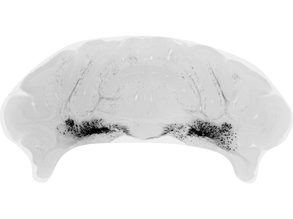

Grey Power